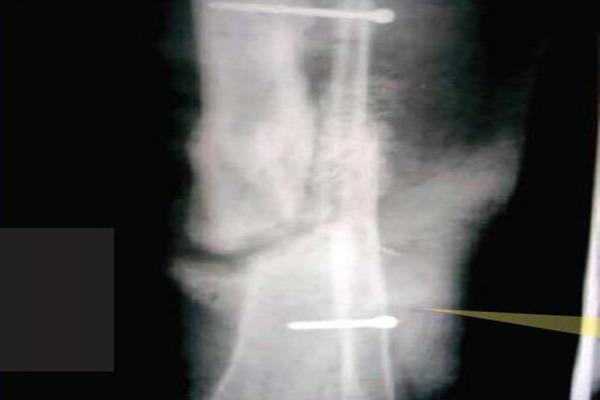

Compound distal tibia fractures have high incidence of nonunions and have varied presentation as far as status of fibula is concerned. If fibula is sufficiently healthy we can use it for bridging the nonunion of tibia.

We present a case of 20 year old female with compound and segmental tibia fracture. Primary stablisation by external fixation and later cast brace application achieved union at the proximal end of the segmental fragment with non union at the distal end. This was then treated with bridge grafting of fibula and screw fixation of fibula to the tibia. Five years follow shows good clinical and functional outcome without any complications.

Its infrequent to find fibula spanning across the tibia nonunion, however when available this can be used as bridge graft to promote healing.